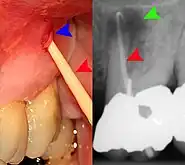

Gutta-percha point indicating abscess origin